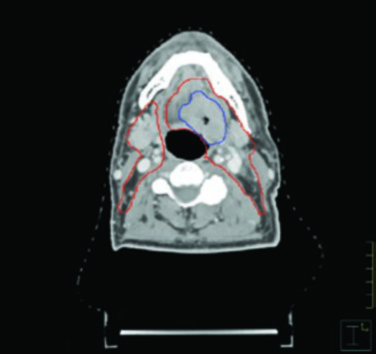

Las figuras de este capítulo ilustran casos reales que ejemplifican los principios de delineación discutidos. El caso de carcinoma amigdalino VPH-negativo cT4N2 demuestra la necesidad de cobertura hasta las láminas pterigoideas e inclusión del nivel IB ipsilateral por invasión de la lengua oral. Observe cómo el GTV (azul) y el CTV (rojo) se adaptan a las barreras anatómicas, respetando hueso y aire mientras se expanden generosamente hacia los tejidos blandos.

El caso de base de lengua VPH-positivo cT4N1 ilustra la cobertura hasta la base del cráneo en el lado N-positivo y la extensión del CTV para considerar cobertura bilateral del nivel IB cuando el tumor cruza la línea media. La vista sagital demuestra con particular claridad la importancia de la cobertura del espacio preepiglótico en tumores de base de lengua — un área frecuentemente subestimada por planificadores menos experimentados.